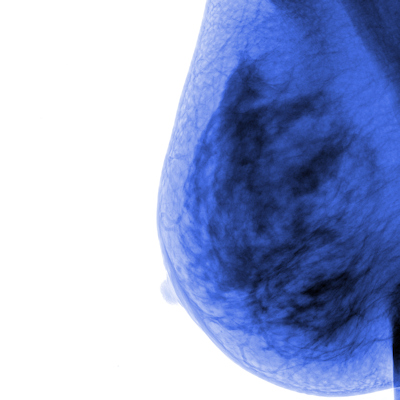

Fears about contracting and spreading COVID-19 led to delays in lung, breast, and colorectal cancer screening during the pandemic among Asian American women, researchers have found.

Over the last 20 years, the Asian population in the U.S. has grown by 72%, and cancer is the leading cause of mortality among it, the team noted. Although Asian American women have traditionally been considered low risk for adverse cancer outcomes, studies have demonstrated "greater exposure to environmental carcinogens and lower cancer screening rates compared with other groups," Vo and colleagues explained.

Vo's group investigated any links between pandemic-related health concerns and cancer screening among 166 Asian American women via a two-phase study. The first phase consisted of a survey distributed to Asian American women eligible for lung, breast, or colorectal cancer screening to assess delays during the pandemic, concerns about contracting COVID-19, barriers to care, and experiences of discrimination. The second phase consisted of four focus group discussions in which participants were stratified by age and history of delayed cancer screening. Of the study cohort, 67% were first-generation Americans, 65% were employed, and 67% held a master's degree or higher.